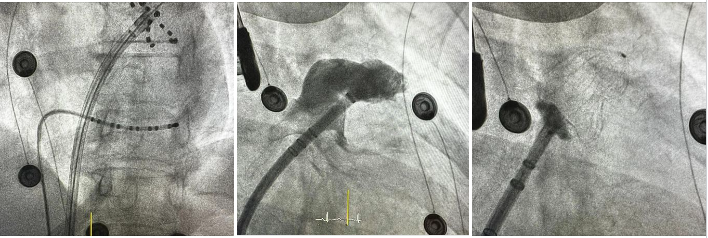

- Ακτινοσκοπική λήψη από την τοποθέτηση του καθετήρα κατάλυσης (FARAPULSE™ Pulsed Field Ablation System) στο στόμιο της αριστερής άνω πνευμονικής φλέβας.

- Σκιαγράφηση του ωτίου του αριστερού κόλπου.

- Επιτυχής τοποθέτηση της συσκευής σύγκλεισης στο ωτίο του αριστερού κόλπου.